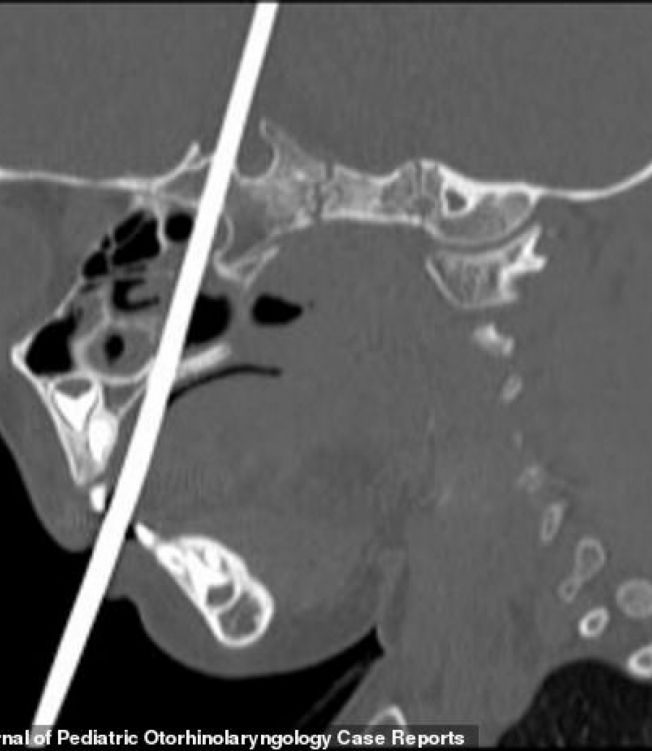

Criança de 3 anos sobrevive após agulha de tricô perfurar seu cérebroReprodução / International Journal of Pediatric Otorhinolaryngology

Ela foi levada às pressas ao hospital, que fica em Utah, nos Estados Unidos, e os médicos descobriram que a agulha atingiu a hipófise e o hipotálamo, regiões responsáveis por hormônios e pela coordenação dos movimentos do corpo. Por mais que ela estivesse sangrando muito, uma tomografia mostrou que os pequenos vasos sanguíneos dela estavam a salvo.